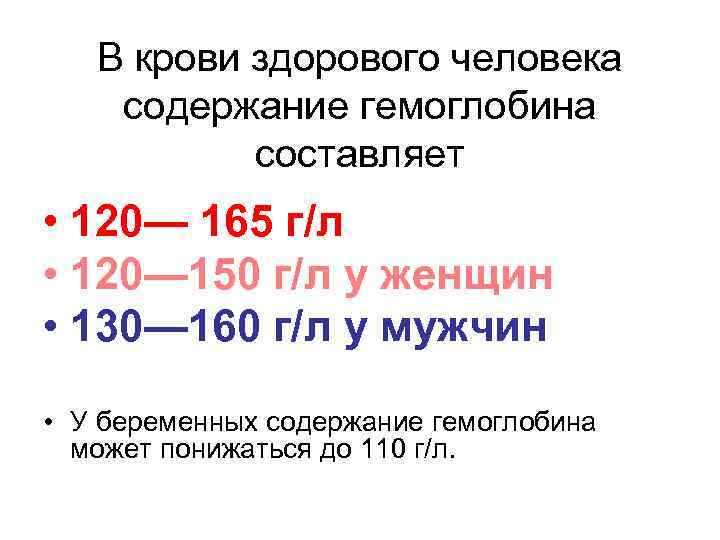

В крови здорового человека содержание гемоглобина составляет • 120— 165 г/л • 120— 150 г/л у женщин • 130— 160 г/л у мужчин • У беременных содержание гемоглобина может понижаться до 110 г/л.

В крови здорового человека содержание гемоглобина составляет • 120— 165 г/л • 120— 150 г/л у женщин • 130— 160 г/л у мужчин • У беременных содержание гемоглобина может понижаться до 110 г/л.